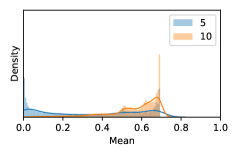

To model how different classifiers will respond to a given input , we assume that the prediction from classifier is sampled from a beta distribution that is characterized by two parameters by and . We further assume that is fixed to the same constant value for all ’s. Under this assumption, each input can be described by ( can be calculated since is fixed), easing further analysis. The Severity Level (SL) of the case represented by image can be characterized by the parameter . The larger the value of , the more severe the case of is. When and are close, the case is ambiguous as the distribution shifts towards being symmetric (i.e. signifying much disagreement among classifiers) rather than being one-sided (i.e. consensus among classifiers that is negative or positive). We provide a set of examples in Figure 2 and also Figure S.8 in the supplementary materials showing how the beta distribution can be used to capture diverse predictions given by an ensemble learner.

In contrast, the MC-dropout method showed the worst overall performance among the three, as it can be seen from the high ratios of SL0 examples among the uncertain negatives in Figure 4. The histograms in Figure 2 provides another perspective to look into the phenomenon, where a decent proportion of MC-dropout model’s predictions on SL0 inputs entailed low confidence (far from 0 or 1), which from another angle explained why MC-dropout was less specific in terms of lower FNP; many no-DR inputs (i.e. SL0) were erroneously assigned high uncertainty by MC-dropout models.

As discussed in Section 5.1 and Section 5.3 in the main paper, the mean metric and the stacking ensemble will have better performance in the precision (specificity) on the ambiguous data. Here, more detailed results are shown in Figures S.3 & S.6 and Table S.1. Figures S.3 & S.4 show the histograms of the uncertainty score for Kaggle-DR and Messidor-2 datasets that are the in-distribution (i.d.) dataset in our experiment and FigureS.5 & S.6 show the histograms for ImageNet and CIFAR-10 datasets, which is the o.o.d. datasets in our experiment. Each group of histograms contains results from the three evaluated ensemble methods (stacking ensemble, MC-dropout and TTA) and the three uncertainty metrics (mean, var and kl). Additional detailed results not displayed in Figure 4 can be found in Table S.1, which shows the proportion of the data of different SLs varies across different . For comparison, we also included in Table S.1 the results from single learners, and the proportions of data of different SLs (before any selection was made).